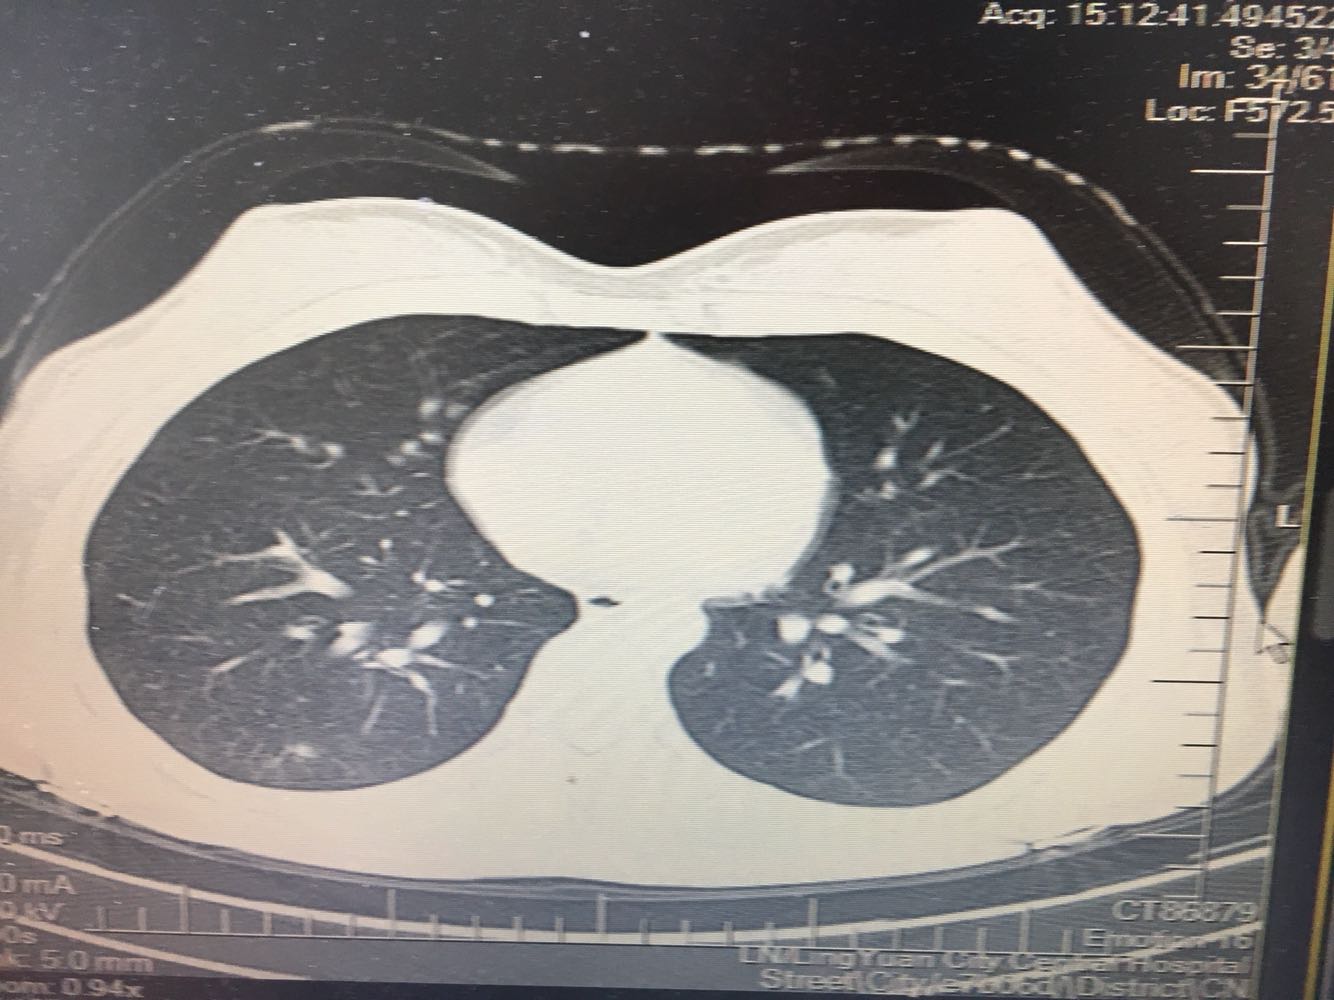

女,26岁,咳嗽1周,咳痰不畅,咽喉痒,口服阿莫西林无好转,昨日发热,体温38.5摄氏度,于门诊查肺CT后以肺炎收入院,病来无盗汗,无咳血,无消瘦及乏力,无头痛,无肢体酸痛,饮食睡眠可,二便正常

支原体肺炎?肺结核?

支原体抗体1:160,结核抗体弱阳性。支原体肺炎个别可见上叶病变,该患无结核中毒症状,考虑支原体肺炎可能性大,但肺尖为结核好发部位,需要抗炎治疗后复查观察疗效。